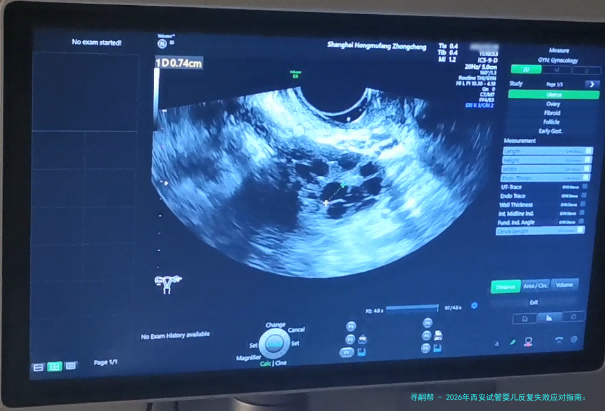

宫腔环境: 通过宫腔镜等检查评介内呈膜样况。

子宫内膜容受性评估(ERA): 通过检测认定的胚胎移植窗口,对片面病患效果突出